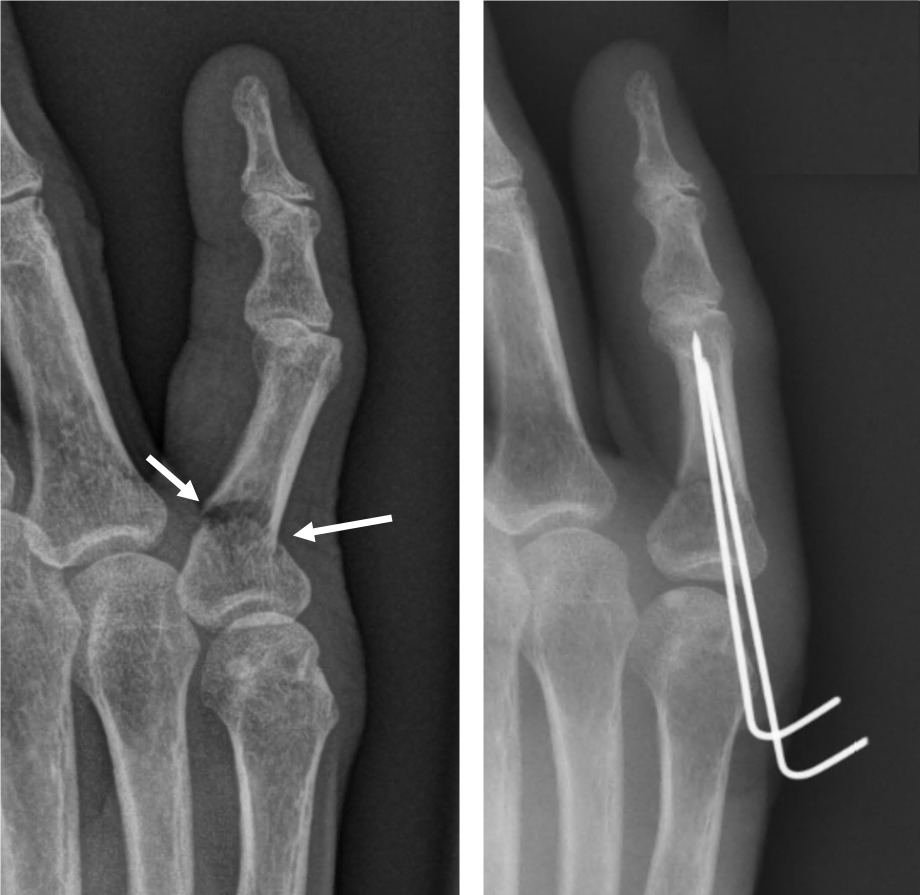

- 적용 시기: 복합 골절, 압박 골절, 뼈 조각이 여러 개로 나뉜 경우처럼 깁스나 스플린트만으로 회복이 어려운 경우.

- 회복 기간: 수술 후에도 2~4주 이상의 안정기가 필요하며, 이후에는 재활 운동이 필수로 따라옵니다.

- 치료 방식: 핀을 박거나 금속판을 대는 방법을 사용합니다. 골절 부위를 정확히 정렬하고 뼈가 잘못 붙지 않도록 하는 것이 핵심입니다.

- 핀 고정 수술

- 뼈가 복합적으로 부러지거나, 어긋나서 그대로 붙으면 기능에 치명적 문제가 예상되는 경우에는 핀이나 금속판을 삽입하는 수술을 진행합니다.

- 수술 후에는 손가락 움직임을 최소화하고, 적절한 시점에 재활 운동을 시작해야 합니다.